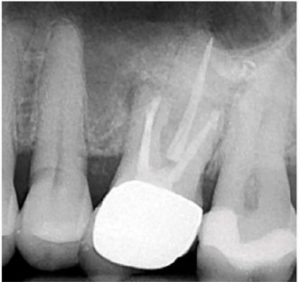

A two-dimensional intraoral radiograph revealed a prior history of root canal therapy and a porcelain-fused-to-metal (PFM) crown (both completed approximately 10years ago) (Figure 2).